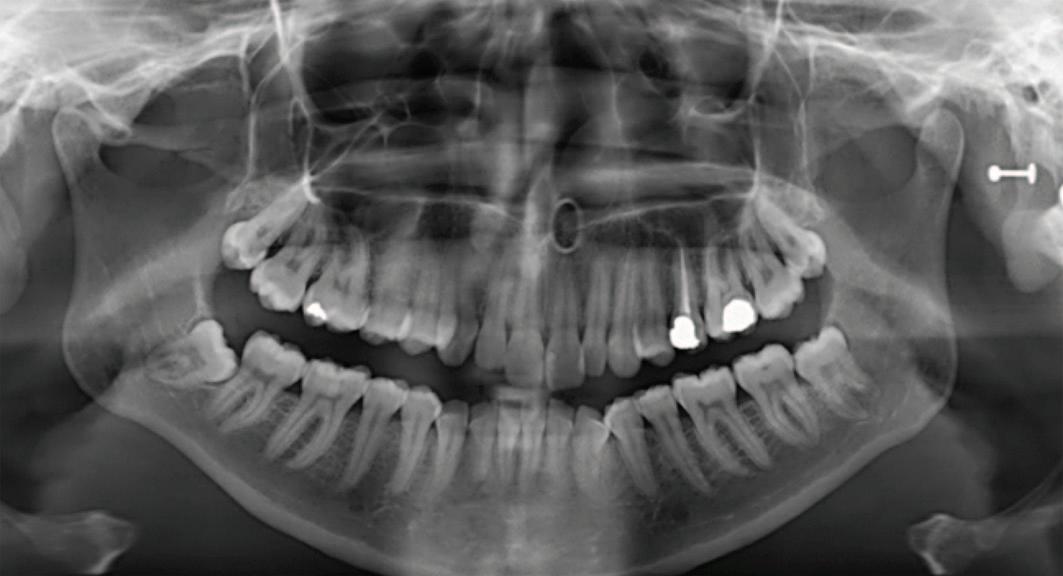

A partially erupted lower le third molar with a prominent operculum was noted during the intraoral examination. The orthopantomogram taken suggested a close relationship of the tooth with the IAN due to a relative rarefaction associated with the distal root, indicating proximity of the nerve canal with little or no bone interposition (Figure 1). Caries was also noted occlusally on the lower le second molar and a deep restoration on the upper le first molar. Following the exclusion

FIGURE 1: Orthopantomogram showing the partially erupted lower left third molar.